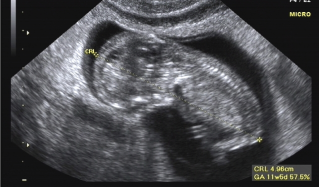

Ultrasonido

Un ultrasonido obstétrico provee imágenes de un embrión o feto dentro del útero de la mujer, como así también como del útero y los ovarios de la madre.